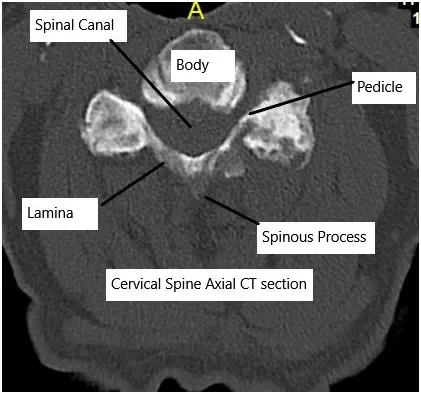

Cervical CT scan showing axial section.

How the Body Part Normally Works? (Relevant Anatomy)

The cervical spine has seven vertebrae separated by discs that act as cushions. Each disc has a tough outer ring (annulus fibrosus) and a gel-like center (nucleus pulposus). These structures allow flexibility and absorb shock. Nerves travel through openings in the vertebrae to the arms and upper body.